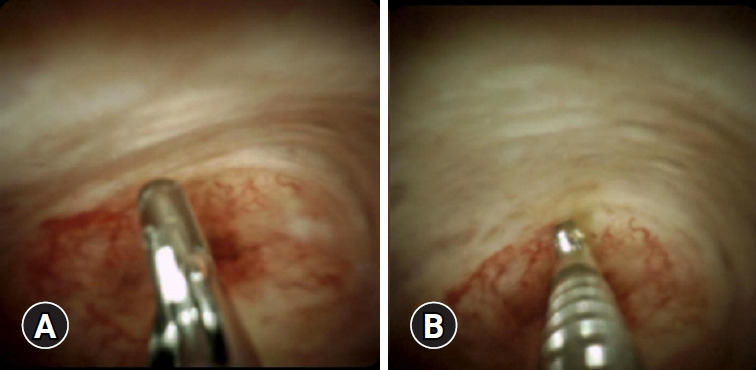

Endoscopic retrograde cholangiopancreatography (ERCP) is the gold standard for the evaluation of biliary strictures and the management of bile duct stones. However, standard ERCP techniques sometimes fail for both indications. In such situations, peroral cholangioscopy (POCS), which allows direct visualization of the bile duct, can play a significant role in diagnosis and treatment. Direct visualization using POCS can help differentiate between malignant and benign conditions and is more accurate in defining the extent of cholangiocarcinoma. Furthermore, POCS enables visually guided biopsies. Certain types of difficult bile duct stones, such as impacted and intrahepatic stones, require POCS for visually guided lithotripsy. Recent advancements in POCS will broaden its applicability and improve its diagnostic utility. In this review, we provide perspectives on the past, present, and future of POCS.